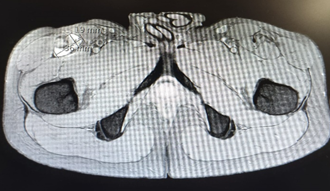

This clinical case concerns a 25-year-old healthy young man, a semi-professional football player who developed pain in the anterior thigh and right inguinal region after a hip hyperextension movement under load during a football game. Following the event, he presented a limp, with his trunk in anterior flexion, as he could not tolerate the neutral position. He experienced pain during resisted hip flexion and in the knee flexion/extension movements. At the time of the event, he reported moderate to intense pain using the numeric rate scale (NRS 7/10). After 36 hours, he underwent a musculoskeletal ultrasonography (US) that showed signal alteration at the myotendinous junction of the sartorius and rectus femoris muscles, highlighted in Figure 1 by a dashed red circle, consistent with a probable myotendinous rupture of the rectus femoris, as well as the presence of a hematoma, indicated in Figure 2 by the red arrows. At the time of the US, there was a slight improvement in pain (NRS 5/10). After 72 hours from the incident, a bruise developed on the anterior thigh, as illustrated in Figure 3.

He underwent pharmacological treatment with paracetamol 1000mg every 12 hours, along with physiotherapy treatments, which included ultrasound, draining massage, compression, and dynamic ice therapy. He also received one session of moist heat, but this exacerbated the bruise, leading to the suspension of further treatment. Two weeks after the injury, he underwent a Magnetic ressonance imaging (MRI) of the thigh, which showed an extensive proximal rupture of the right rectus femoris muscle, with a hematoma measuring approximately 61 * 36 * 19, as outlined by the dashed yellow circle in Figure 4. He did not undergo a period of rest and started quadriceps strengthening exercises 3 weeks after the injury due to the absence of pain while walking. Currently, in the 4th week after the event, he is pain-free while walking, with no limitations or pain in active hip and knee movements. He is tolerating concentric and eccentric quadriceps exercises using only body weight, experiencing pain only during the passive stretching of the quadriceps.